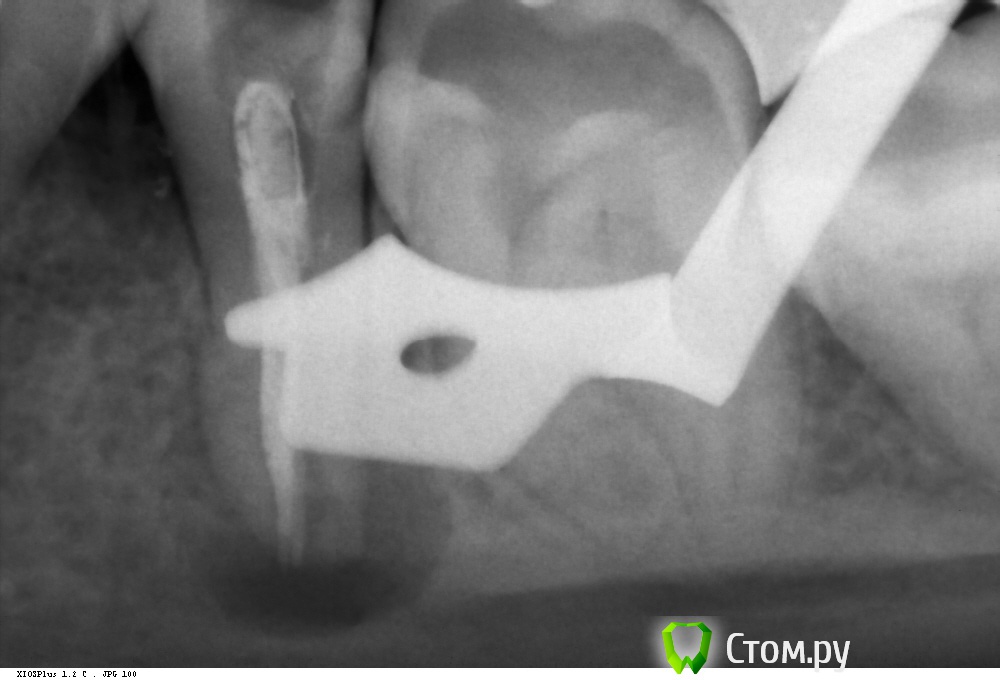

Shaid Опубликовано 9 марта, 2014 Поделиться Опубликовано 9 марта, 2014 (изменено) Пациентка, 14 лет обратилась с постоянной ноющей болью в 35 зубе, болями при накусывании.Объективно: пломба на жевательной и дистально-контактной пов-ти. В канале гуттаперча. Перкуссия +.Распломбировал гутту(оставил часть в апексе, потому что не смог вытащить, а время приема заканчивалось), промыл(кровило), оставил кальций.Какова дальнейшая тактика в данном случае?Стоит ли ждать формирования апекса(вести через кальций) или на следующее посещение закрыть мта? Нужна ли РВК? Кому в апексе видится латераль? Изменено 9 марта, 2014 пользователем Shaid Ссылка на комментарий

Каплан Опубликовано 9 марта, 2014 Поделиться Опубликовано 9 марта, 2014 (изменено) больше похожу на глубокий сплит.. как на 5ке на моем снимкеhttp://imagizer.imageshack.us/v2/xq90/28/2xk1.jpgпричем в твоей ситации первый доктор пропустил этот сплит можно конечно вычистить гутту и постараться вытянуть зуб через реваскуляризацию... но не уверен что получится при перелечивании... она и так-то не очень успешная... на апексогенез особо не расчитывал бы.скорее всего провел бы на кальций и апикальная пробка из мта. хотя вполне можно и гуттаперчу, только откалибровать. Изменено 9 марта, 2014 пользователем Каплан Ссылка на комментарий

Kolchanov Опубликовано 9 марта, 2014 Поделиться Опубликовано 9 марта, 2014 14 лет обратилась с постоянной ноющей болью в 35 зубе Когда зуб был лечен впервые? больше похожу на глубокий сплит.. Думаю, что все проще. Зуб помер или ему помогли помереть в стадии незакрытой верхушки. И сформироваться ей уже не дано. Это довольно сложный зуб и я бы донес до родителей информацию об этом. Если будут готовы, то послать, но послать желательно адресно к тому, кто сможет это сделать. Только в случае отказа (желательно письменно это дело закрепить, что мол зуб сложный и т.д.) браться самому. После полного удаления гуттаперчи есть снимок? 1 Ссылка на комментарий

Shaid Опубликовано 10 марта, 2014 Автор Поделиться Опубликовано 10 марта, 2014 Это довольно сложный зуб и я бы донес до родителей информацию об этом.Донес. но послать желательно адресно к тому, кто сможет это сделать.Имеете ввиду микроскописта? После полного удаления гуттаперчи есть снимок?Полного удаления гуттаперчи не было) в апексе осталось. Есть только такой снимок(с кальцием), хотя ничего информативного, на мой взгляд, он не несет. Ссылка на комментарий

Kolchanov Опубликовано 10 марта, 2014 Поделиться Опубликовано 10 марта, 2014 Клади не контрастный гидроксид, если хочешь посмотреть сколько старого материала осталось. Кальсепт, например.Даже когда на рентгенограмме все пучком, заглянешь с оптикой в канал и удивишься, сколько там еще осталось по стенкам. Микроскоп бы хорошо. Не будешь же гуттаперчу в апексе в Триоксидент вмуровывать.Какой там размерчик получился? По снимку кажется, что и 140 пролетит. 1 Ссылка на комментарий